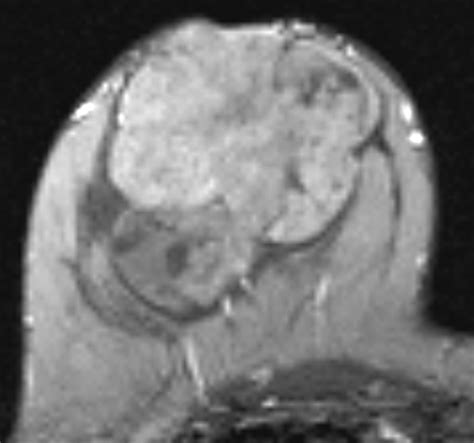

A Phyllodes tumor breast is a rare type of fibroepithelial tumor that originates in the connective tissue of the breast, known as the stroma. Unlike breast carcinomas, which arise from the milk ducts or lobules, these tumors grow within the supportive structural tissue. The term "phyllodes" comes from the Greek word for "leaf-like," which describes the specific pattern in which these tumors grow under a microscope.

These tumors are generally characterized by their rapid growth. While the vast majority are benign, some can be borderline or malignant. Because they can grow quite large and may recur if not completely removed, accurate diagnosis and appropriate surgical intervention are essential.

To differentiate a Phyllodes tumor breast from other breast conditions, clinicians employ a multi-modal diagnostic approach. Since imaging alone cannot definitively distinguish a phyllodes tumor from a fibroadenoma, a biopsy is typically required.

2. Imaging (Mammography/Ultrasound): Provides detailed views of the tumor's size, shape, and borders.